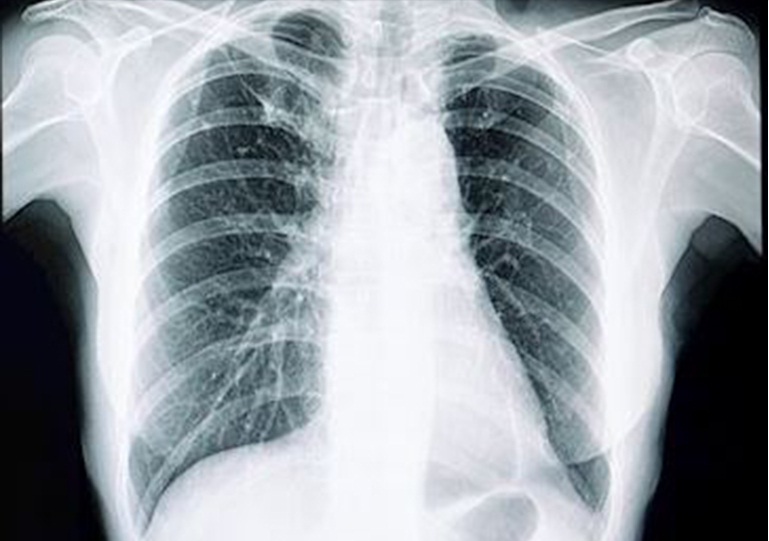

Una vez en los bronquios, el virus causa que las mucosas pulmonares se inflamen y se dañen los alveolos. En consecuencia, el proceso de oxigenación de la sangre se ve afectado. Estos dos factores, en ocasiones, pueden llevar a que las zonas afectadas de los pulmones se llenen de fluido, pus y células muertas, hasta el punto de provocar una neumonía, recoge el medio estadounidense. UN